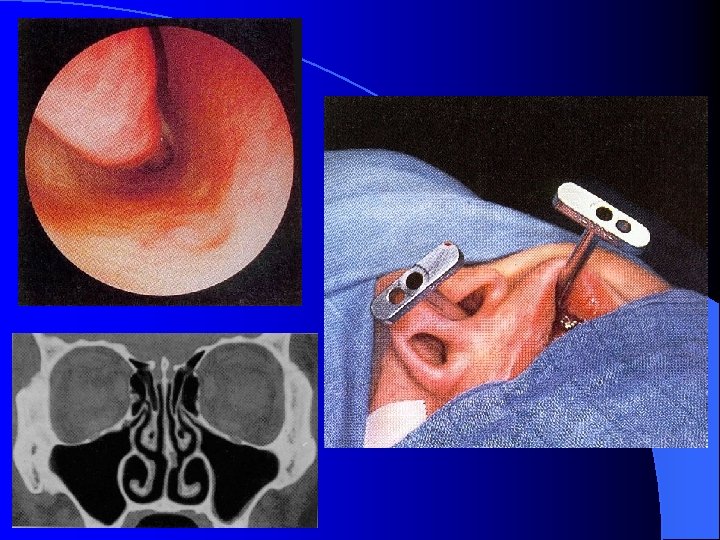

MALADIES INFECTIEUSES RHINO SINUSIENNES SINUSITE MAXILLAIRE CHRONIQUE TRAITEMENT Prise en charge Médico-Chirurgicale • Lavage des fosses nasales • Vaso-constricteurs locaux • ATB probabiliste orale 21 jours • Méatotomie moyenne endonasale • Voie vestibulaire type Caldwell-Luc Objectif: • Levée de l’obstacle ostial • Prélèvements bactério et anapath (Dc différentiel) • Suppression du foyer infectieux (truffe aspergillaire, foyer dentaire)

MALADIES INFECTIEUSES RHINO SINUSIENNES SINUSITE MAXILLAIRE CHRONIQUE FORMES CLINIQUES SMC Aspergillaire: • ATCD de soins dentaires maxillaires • RX, TDM: Micro-opacité de tonalité métallique au sein d’une opacité complète du sinus maxillaire • Prise en charge chirurgicale : Méatotomie moyenne endonasale pour détersion du sinus maxillaire et exérèse de la truffe aspergillaire Voie vestibulaire type Caldwell-Luc • Aucune indication à un traitement médical antimycosique SMC de l’enfant: (rare) Contexte de pathologie générale à recher Mucoviscidose, Dysfonction ciliaire (Kartagener)

Forme extériorisée = TDM

MALADIES INFECTIEUSES RHINO SINUSIENNES ETHMOIDITE AIGUË IMAGERIE • Radiographie standard • Echo doppler couleur (opérateur dépendant) • TDM sans et avec injection siège, stade collecté, analyse orbitaire fine